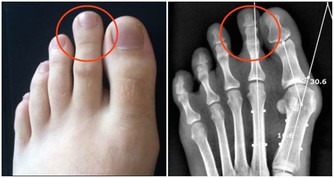

2、任天堂關節炎(Nintendo Arthritis)